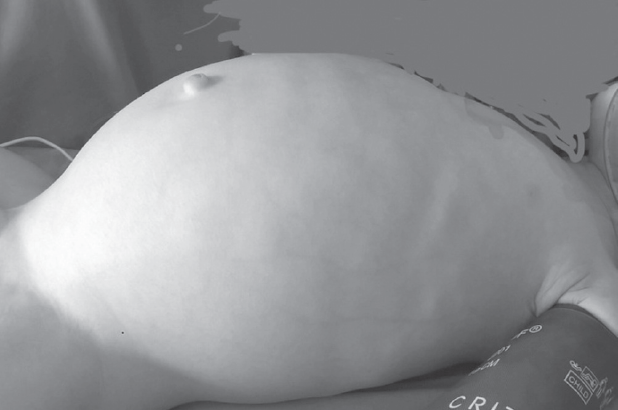

Доношенный полновесный ребенок поступил на 5-е сут жизни в стационар с жалобами на вздутие живота, срыгивания с примесью желчи и отсутствие стула. На обзорной рентгенограмме брюшной полости выявлено равномерное распределение газа по кишечнику без уровней жидкости и раздутая на всем протяжении газом толстая кишка (рис. 1, 2).

Рис. 1. Обзорная рентгенограмма брюшной полости

Fig. 1. Plain abdominal X-ray

Рис. 2. Вид живота перед операцией

Fig. 2. Abdomen view before the surgery

После выполнения высокого промывания толстой кишки отошло большое количество кашицеобразного стула и газов, живот уменьшился в размерах. Диагноз кишечной непроходимости был исключен. В последующие дни ребенок не срыгивал, питание усваивал, регулярно отходил самостоятельный стул. Выписан на амбулаторное лечение с диагнозом: гипоксически-ишемическое поражение ценральной нервной системы, вегето-висцеральный синдром. На 2-м месяце жизни появилась тенденция к задержке стула, которая нарастала в динамике. Ребенок наблюдался педиатром и ни разу не был осмотрен хирургом. В хирургический стационар поступил в возрасте 10 мес. с клиникой кишечной непроходимости (рис. 2).

Ярким примером недооценки клинической картины служит случай 1. Отсутствие ярких симптомов кишечной непроходимости и эффективность очистительной клизмы позволили уже в первые дни жизни исключить у ребенка хирургическую патологию. Травматичные роды и использование вакуум-экстракции для родоразрешения стали основой для ошибочной интерпретации его состояния. Пациент наблюдался как ребенок с парезом кишечника на фоне черепно-спинальной травмы. На обзорной рентгенограмме брюшной полости расширение толстой кишки на всем протяжении было недооценено. Наличие «светлого» промежутка, характеризующегося отхождением стула, полностью исключило какие-либо подозрения на хирургическую патологию. Ребенок был выписан на амбулаторное лечение педиатром без рекомендации дальнейшего наблюдения хирургом. Следует отметить, что подозрение на кишечную непроходимость, задержку отхождения мекония и расширение толстой кишки при рентгенологическом исследовании у детей первых дней жизни должны наводить неонатолога и тем более хирурга на мысль о возможности болезни Гиршпрунга. В подобных случаях целесообразно выполнять ирригоскопию, которая позволит установить правильный диагноз в большинстве случаев.